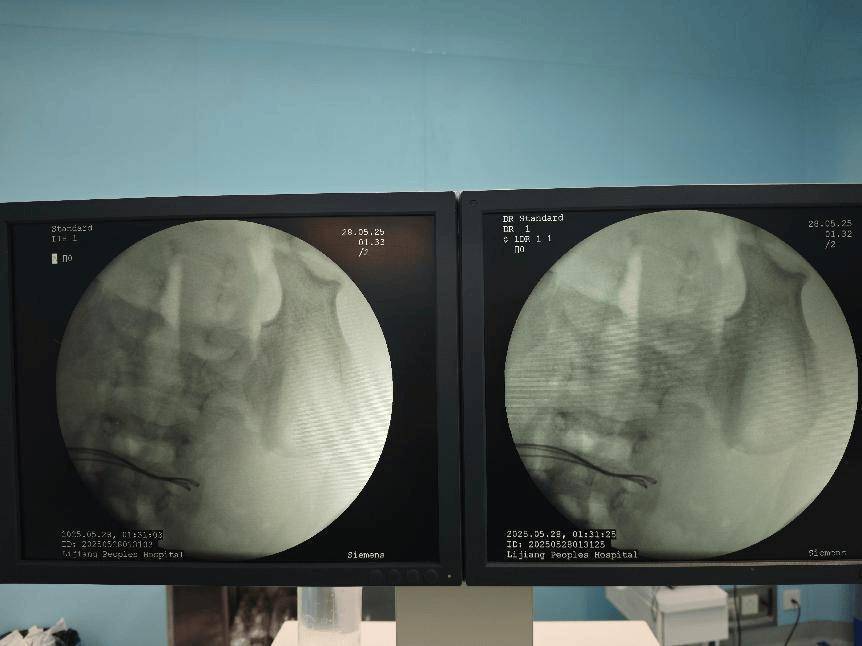

经过初步的影像学检查,医疗团队发现:病人体内竟然有37颗异物,连在一起呈手串状,并伴有小肠穿孔拜仁慕尼黑足球 。

术前腹部DR片